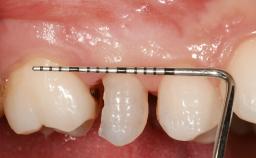

Early Placement of an Implant in a Maxillary Right Central Incisor Site

This 41-year-old female patient was referred to the clinic for the replacement of the right central incisor, since the tooth had developed a root fracture in the long axis that made extraction necessary. The healthy, non-smoking patient was first seen with the tooth still in place. A detailed Esthetic Risk Assessment was performed.The patient was worried about her dental esthetics and had high expectations for a successful treatment outcome from an esthetic point of view. The patient had a medium lip line that displayed parts of the gingiva in the anterior maxilla upon smile.

Lip Line No exposure of papillae Exposure of papillae Full exposure of mucosa margin

Periodontal Phenotype Low-scalloped, thick Medium-scalloped, medium-thick High-scalloped, thin

Soft Tissue Contour and Volume Slightly compromised